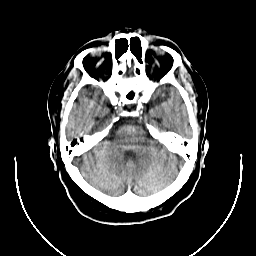

CT Study #1 -- Slice #8